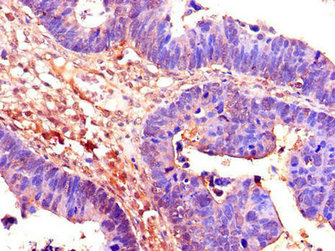

Immunohistochemistry of paraffin-embedded human ovarian cancer using CSB-PA004995LA01HU at dilution of 1:100